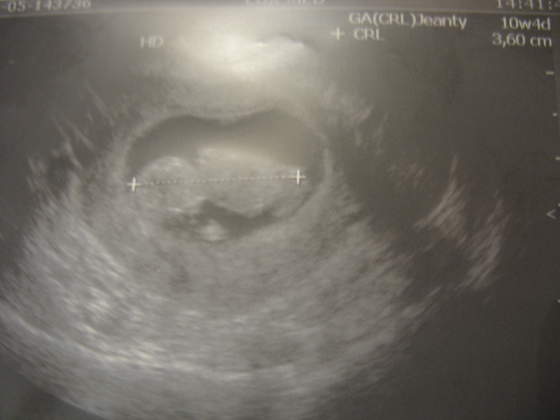

Dziewczynki, byłam dzisiaj u lekarza i dostałam skierowanie na USG. Umóiłam się na jutro, więc wieczorkiem pewnie coś wkleję :-) Nie mogę się doczekać. To będzie zwykłe usg, poznam wymiary i może coś więcej nt rzeczywistego tygodnia ciąży. Potem do 14 tyg zrobię genetyczne, w tym 3D i już nie mogę się doczekać.

Trzymajcie kciuki, zebyśmy jutro zobaczyli że wszystko ok!! Jadę z moim Mkiem - on po raz pierwszy!!Chyba dzisiaj nie usnę z wrażenia hihi